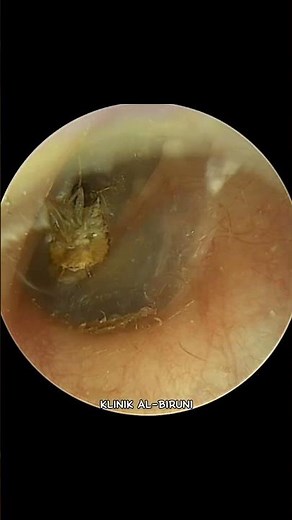

COCKROACH FOUND DEAD IN THE EAR ‼️

57.9K views

Oct 12, 2024

YouTube

Klinik Al-Biruni